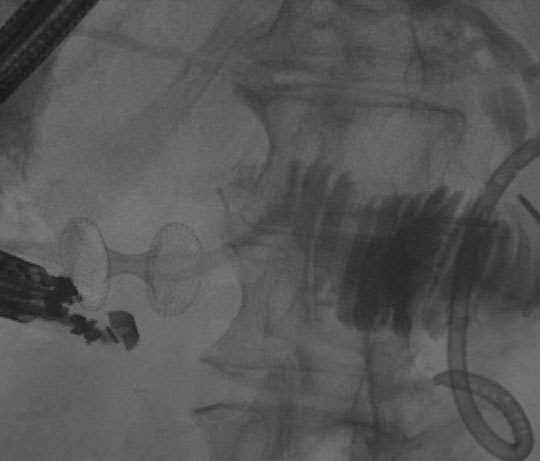

Our faculty have expertise in a wide variety of endoscopic techniques and procedures. The trainee should expect to receive hands-on experience in several procedures and techniques including routine and complex ERCP (e.g. cholangioscopy, pancreatoscopy, hilar biliary obstruction, lithotripsy, ampullectomy), diagnostic EUS, interventional EUS (including transmural drainage of pancreatic fluid collections, celiac ganglion block/lysis, EUS-guided biliary access and drainage, EUS-guided gastroenterostomy), complex resection of large colorectal polyps (including EMR and ESD), enteral stenting, management of leaks and fistulae, endoscopic eradication therapy for Barrett’s esophagus (EMR, RFA), and deep small bowel enteroscopy (single balloon only).